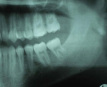

Molar migrations after loss of first molars, 8-year history: 1999

Figure 28

In 1998, a 7-year-old boy was brought in for emergency care with the chief complaint of toothache of the mandibular left permanent first molar. The malformed tooth was non-restorable and extracted, with no other treatment options. The child was not returned for continuing routine care but was returned on an emergency basis in 1999. He had a dentoalveolar abscess of the severely carious maxillary left permanent first molar, and the tooth was judged non-restorable (Figure 28). That molar was extracted. The patient was not returned to the office again until 4 years later, in 2003. The maxillary second molar had migrated into good position distal to the second premolar, and the third molar followed into place (Figure 29). The mandibular second molar was tipped mesially, followed by the crown of the third molar. Four years after that (2007), the patient returned as a 15-year-old. The second and third molars had migrated into position, with no orthodontic intervention (Figure 30).